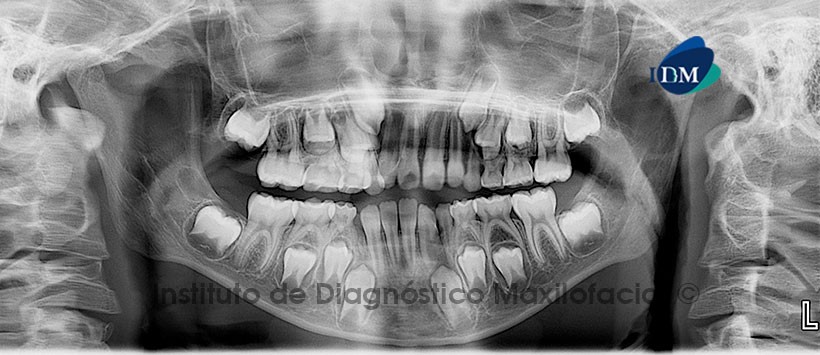

Paciente masculino, 11 años de edad es referido al Instituto de Diagnostico Maxilofacial (IDM) para evaluación general.

A la evaluación de la radiografía panorámica (ortopantomografía) se aprecia las estructuras óseas adyacentes conservadas, así como opacidad en la totalidad de ambos senos maxilares y desviación de la línea media (Figura 1)